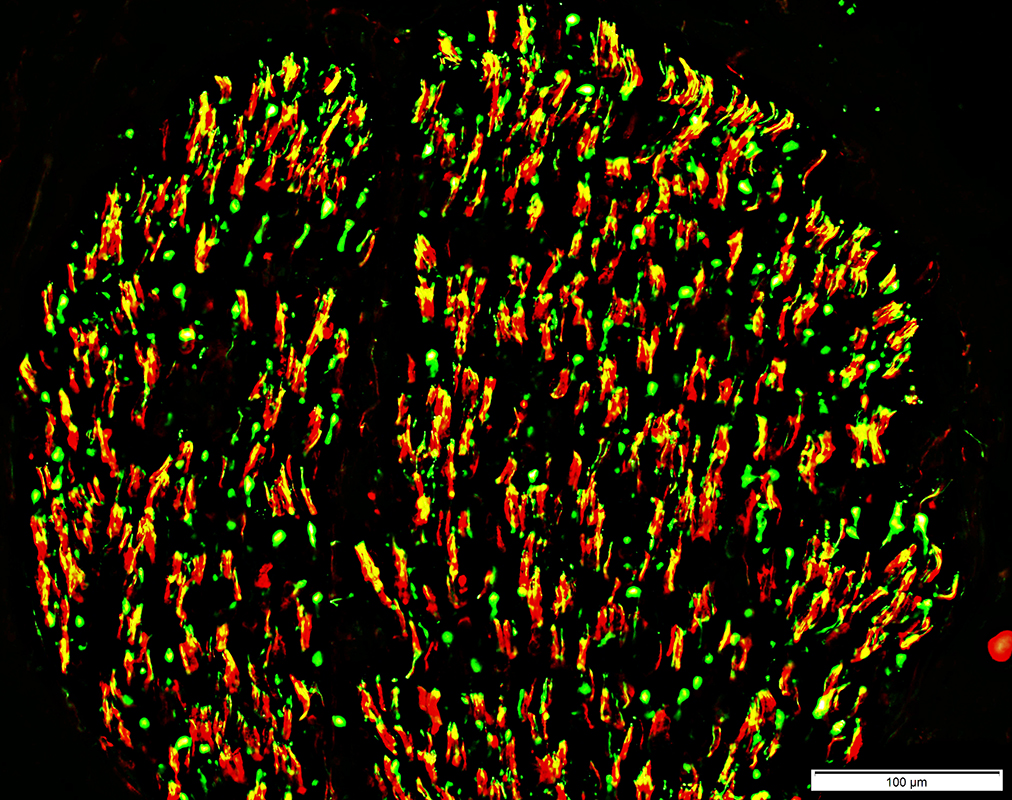

Neurofilament (Green), Myelin basic protein (Red) stain

Neurofilament stained axons in sural nerve (Yellow)

Lost within many MBP stained myelin sheaths (Red)

Unmyelinated Axons: preserved numbers (Green)